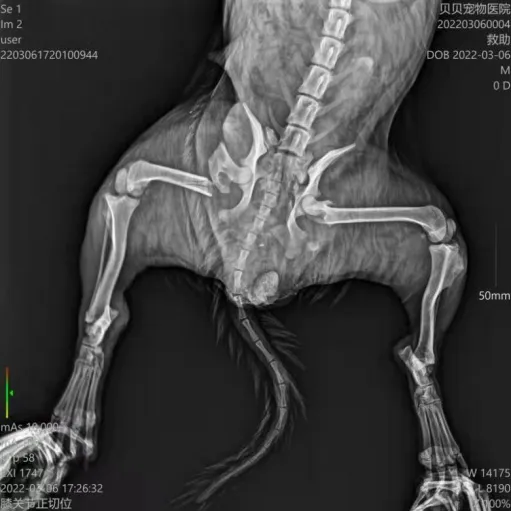

3月6日领养日的时候接到求助,救助组组长广陵糖与其他成员一同前往现场救助,送院后拍片结果为后脚和盆骨都有骨折,目前狗狗已经做完手术恢复良好,但后腿残疾无法送养,协会基地接收。